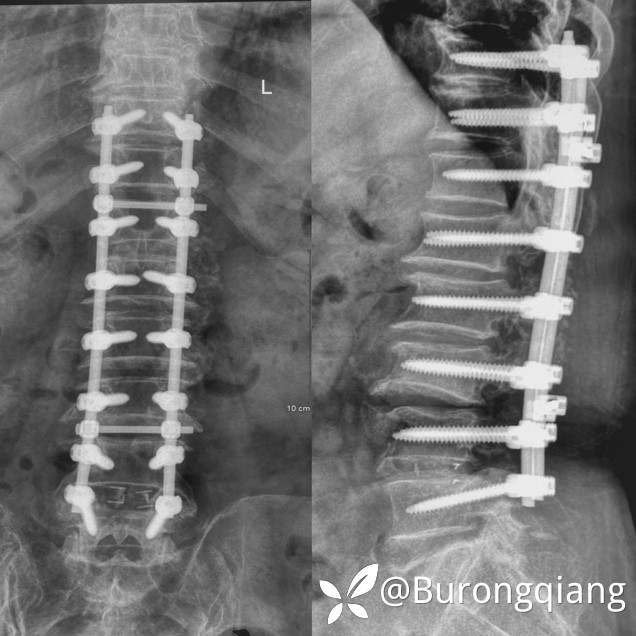

简要病史:患者述2年前无明显诱因出现双下肢大腿憋胀不适症状。外院进一步检查后诊断胸腰椎椎管狭窄,于外院行胸腰椎多节段椎管减压内固定手术治疗,术后症状改善明显,术后10个月再次逐渐出现双下肢麻木无力症状,左侧症状明显,行走时偶有打软腿不适,1年前摔倒致左踝关节骨折,给予内固定手术治疗,术后一直未能下地活动,双下肢麻木无力明显,二便正常。采取保守对症治疗,症状近来逐渐加重。

治疗经过:给予脊柱内镜下椎管扩大减压手术治疗。

术后复查